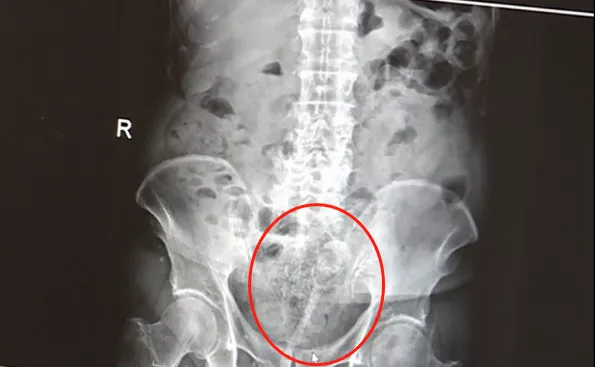

随后,王伯被120救护车送到浙大一院庆春院区急诊科。此时,他的血压降至80/50mmHg,意识已开始模糊。

急诊科医生快速检查后,倒吸了一口凉气:直肠粘膜被捅破,血流不止,粪便污染引发局部感染,出血速度已经接近失血性休克的临界值!

急诊科医生立即对王伯进行抗失血性休克治疗,经过开通静脉通路、补液、输血等一系列抢救措施,维持住了王伯的生命体征。

但因王伯本身患有高血压、慢性心功能不全、肾功能不全等多种基础疾病,这一意外无疑雪上加霜。结直肠外科专家团队紧急出动,折腾了一个多小时,才成功止血。

这次,可能由于太着急了,王伯没控制好力道,大便没能解出来,却用筷子把直肠壁给戳破了。